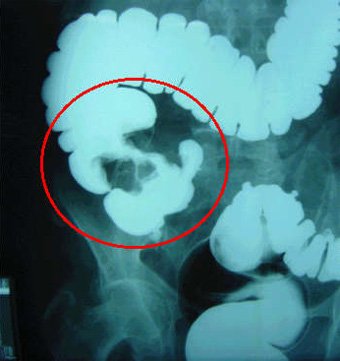

El enema opaco es una técnica diagnóstica que nos permite visualizar el intestino grueso (colon) mediante el uso conjunto de rayos X y un agente de contraste (Bario y/o aire). Este contraste se administra por vía rectal en el momento de realizar la prueba.

Mediante el enema opaco podemos estudiar como es la anatomía de su intestino y si existe algún tipo de patología en el mismo: inflamación, pólipos, tumores, etc.

Una vez preparado el colon y vacío completamente de heces, se podrá examinar adecuadamente tanto la forma del mismo (anatomía) como la existencia de posibles patologías que asienten a este nivel. Para ésto se le conducirá a la sala de radiología y se le pedirá que se tumbe en una mesa de exploración radiológica. A continuación se le introducirá una cánula a través del recto, por la cual se administrará un agente de contraste (Bario). Se le inyectará la cantidad de bario que sea necesaria para rellenar el colon en su totalidad y visualizar sus diferentes regiones anatómicas: recto, sigma, colon descendente, colon transverso, colon ascendente y ciego. Para rellenar con contraste todo el colon y hacernos una idea más clara del estado del mismo, puede ser necesario que cambie de posición en la mesa de radiología durante la prueba, o que incluso el radiólogo tenga que cambiar la situación de la mesa o su inclinación.

Mediante la "técnica de contraste simple" (Bario) se rellena el interior del colon, dándonos una idea de su morfología, anatomía y de si existen lesiones en el mismo. Mediante rayos X se estudiará dicha anatomía y si existen posibles patologías. Los hallazgos de la prueba (enema opaco) se documentarán mediante la realización de radiografías del colon, tomadas en diferentes ángulos y en distintos momentos de la exploración.

En ocasiones puede ser útil realizar una "técnica de doble contraste". Esta técnica consiste en rellenar el colon mediante la administración de Bario en un primer momento y luego, tras ser expulsado éste, administrar aire (segundo método de contraste). La peculiaridad de esta técnica consiste en que el bario administrado inicialmente, se adhiere a la pared del colon y mediante la distensión del colon proporcionada por la administración posterior de aire, se hacen más patentes los pequeños defectos de la mucosa (úlceras de la Enfermedad Inflamatoria Intestinal, pólipos de pequeño tamaño difíciles de visualizar). Por el contrario, el enema de contraste simple (sólo contraste con Bario) es la técnica de elección en caso de que exista sospecha de una lesión obstructiva en el colon (pólipos, cáncer), divertículos o colitis isquémica.